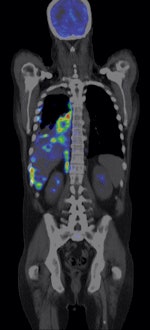

![]() |